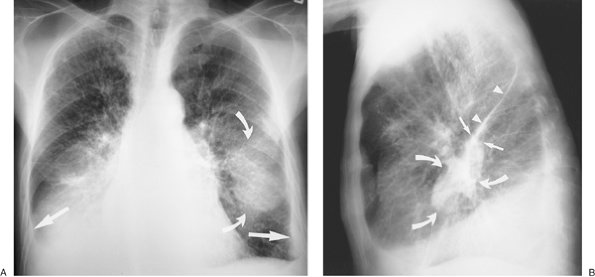

FIGURE 9-7. Pulmonary edema and pleural fluid pseudotumor. A: PA chest radiograph shows enlargement of the cardiac silhouette, interstitial pulmonary edema, and displacement of the inferolateral lungs from the chest wall and diaphragm by pleural effusion (straight arrows). There is a hazy "mass" in the left middle and lower hemithorax (curved arrows). B: Lateral chest radiograph shows that the "mass" or "pseudotumor" (curved arrows) blends in with the left major fissure (straight arrows); this is characteristic of pleural fluid within the fissure. The superior aspect of the left major fissure is thickened as a result of pleural fluid and subpleural edema (arrowheads).